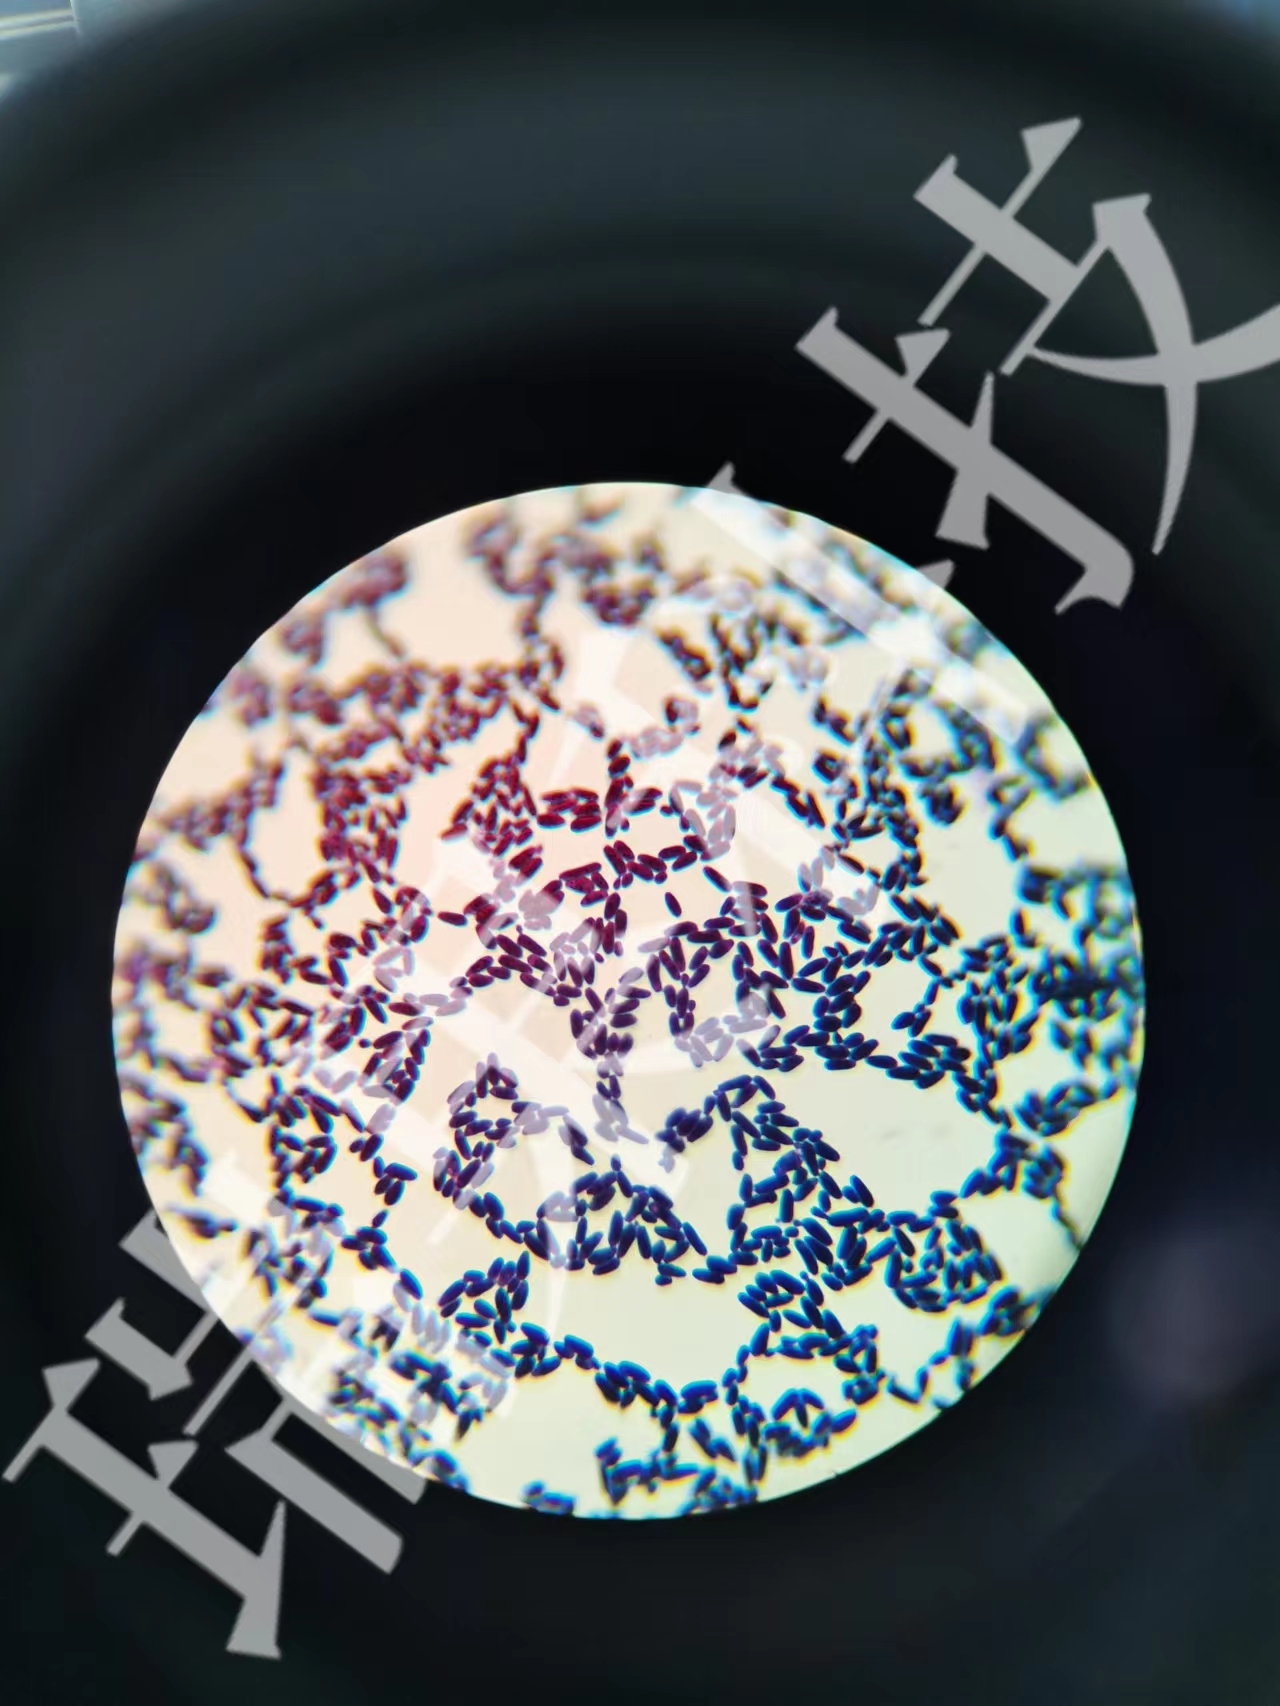

过碘酸—雪夫染色

过碘酸-雪夫(Pexiodic acid-schiff,PAS)染色又称糖原染色。胞浆内存在的糖原或多糖类物质(如黏多糖、黏蛋白、糖蛋白、糖酯等)中的乙二醇基(CHOH-CHOH)经过碘酸(Periodic acid)氧化,转变为二醛基(CHO-CHO),与雪夫(Schiff